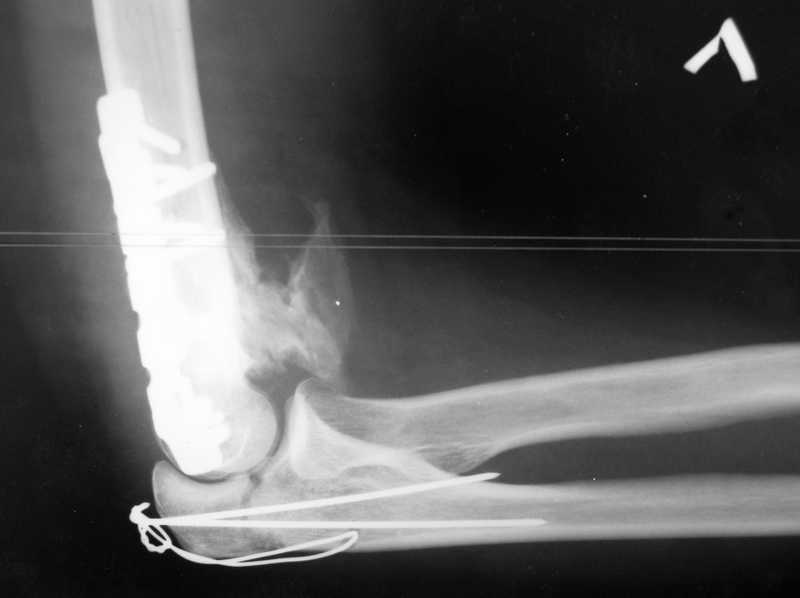

У пациентки 42 лет после операции остеосинтеза чрезмыщелкового перелома плеча, выполненной в нашей клинике 2 месяца назад, на контрольных R-граммах имеется гетеротопический оссификат по передней поверхности плеча.

Оперирована по методике АО, после операции максимально рано начала заниматся ЛФК. В настоящее время основная жалоба пациентки на ограничение сгибания в локтевом суставе. Клинически объем движений: сгибание 90 градусов, разгибание 170 градусов, ротационные движения в полном объеме. Привожу снимки сразу после операции и через 2 месяца. (На рентгенограммах после операции в мягких тканях по передней поверхности плеча имеется небольшой костный фрагмент, но его ширина во фронтальной плоскости не более 1 мм., обнаружен был по снимкам после операции. Интраоперационно основные крупные фрагменты отрепонировались хорошо, объем движений был сгибание до 75 градусов, разгибание 175 град.) Пациентка неудовлетворена объемом сгибания, хотя была предупреждена о высокой вероятности ограничения движений. Профилактика гетеротопической оссификации (прием индометацина) не проводилась, т.к. имелась язвенная болезнь, да и эффект от его приема считаю сомнительным.